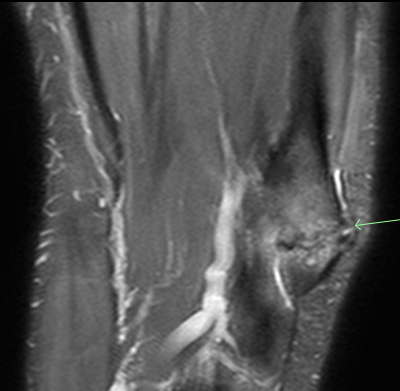

#CaseOfTheWeek‼️🥳‼️ ☢️🩻☠️Case#22☠️🩻☢️ #Mass 📲➡️➡️#Diagnosis❔❓❔ #FOAMRad #RadEd #MedEd #OrthoEd #OrthoTwitter @ssr_rwg @UWRadRes @ISSVA_org